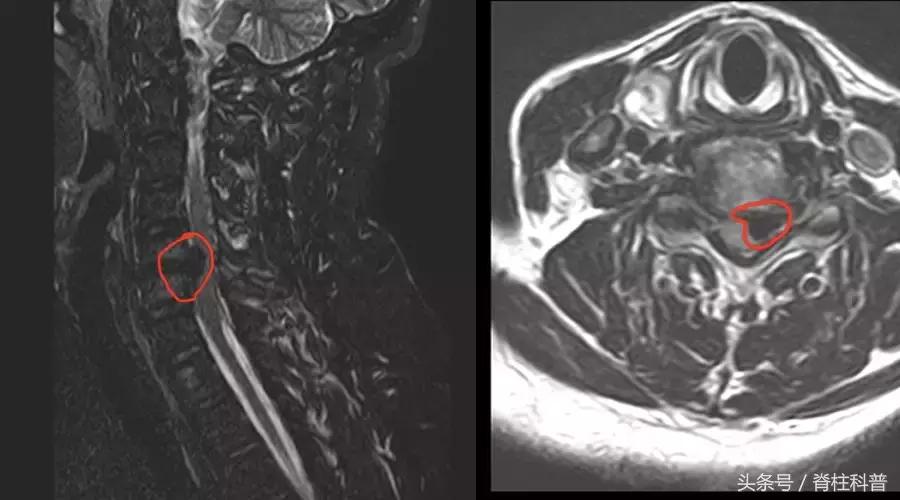

简样的MRI片子

于是,去汕尾某医院看医生的。当时给拍了MRI,结果显示:

椎间盘突出(第3椎体和第4椎体间的椎间盘、第5椎体与第6椎体间的椎间盘突出);后纵韧带及黄韧带增厚(第5颈椎及第6颈椎水平后纵韧带及黄韧带增厚)等。